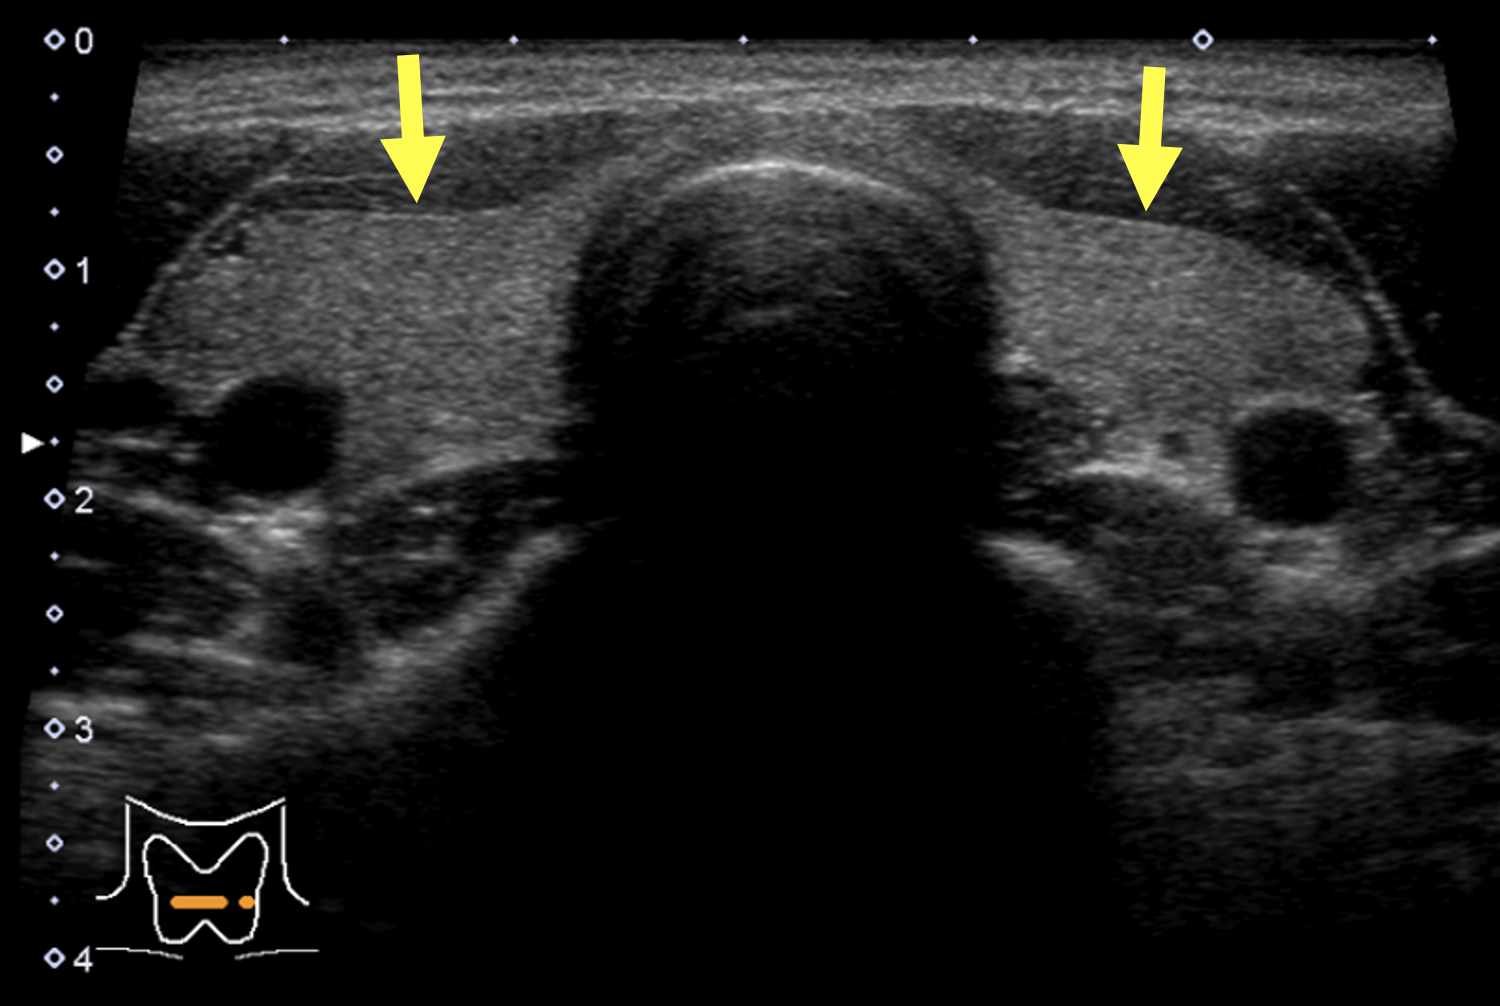

慢性甲状腺炎(橋本病)

慢性甲状腺炎(橋本病)甲状腺の表面がデコボコしています。

甲状腺全体が腫れて大きくなります。

甲状腺の内部が黒っぽくなり(エコーレベル低下)、むらがあります(内部不均質)。

※軽症の場合は正常な甲状腺とほとんど変わらない場合もあります。